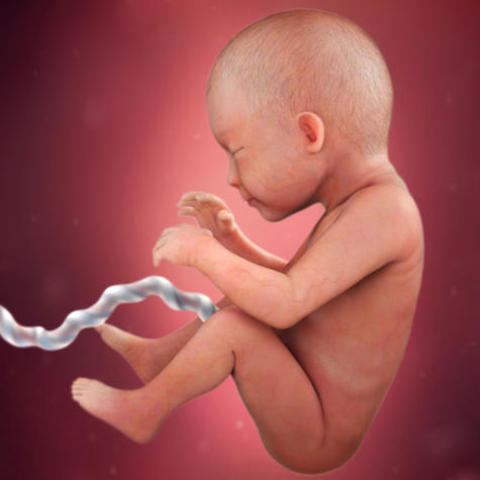

The mass of cells is now a fetus, a szie of a small strawberry and your staring to gain weight, but not from all the choclaate cake you've been eating. Muscles, organs and reproductive organs are begining to devlope.

The prostate gland is devloping inside your baby boy and guess what, he can pee! The fetus' skin is transparent and hair is growing.

The bone marrow is now making blood cells as their small intesine begins to work to absorb nurishment, not junk. The testis begin to form but remember, sperm doesn't get produced until he hits that wonderful, confusing stage in life; puberty.